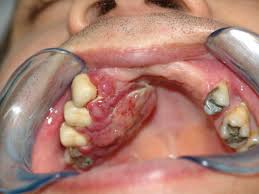

Câncer de boca no Brasil

O câncer bucal no Brasil tem alta incidência, constituindo um importante problema de saúde pública. No entanto é uma doença que poderia ser controlada através de uma menor exposição aos fatores de risco e de um diagnóstico precoce.

De incidência e de morbidade, o Carcinoma Epidermóide encontra-se, entre os índices de câncer oral, mais elevados do mundo.

Os fatores mais influentes para o desenvolvimento do câncer bucal são o álcool e o tabaco em qualquer de suas formas. Herranz González- Botas (2001) asseguram que 95 % das neoplasias malignas da boca são carcinomas epidermóides, que acometem pessoas do gênero masculino, de cor branca, com idade superior a 50 anos, com baixa renda e grau de instrução precário, com maior incidência na língua, sendo um importante problema de saúde pública, cujas taxas